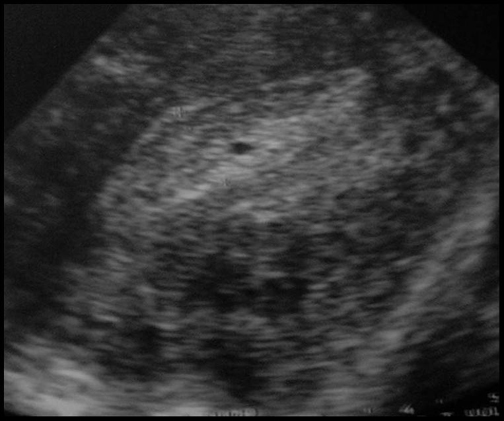

Muqueuse hétérogène